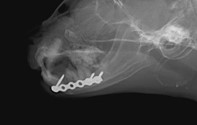

眼球摘出、眼瞼腫瘤切除、チェリーアイ整復、眼瞼縫合、瞬膜フラップ、眼球突出整復、耳介切除、垂直耳道切除、総耳道切除、鼻鏡切除、口腔腫瘍切除(上顎骨切除、下顎骨切除を含む)、各種抜歯(猫の全臼歯抜歯含む)舌腫瘍切除、唾液腺嚢胞切除、皮膚腫瘤切除、断脚(前肢、後肢、片側骨盤切除)、断尾、肺葉切除、胸腺腫切除、心膜切除、横隔膜ヘルニア整復、肝臓腫瘍切除、胆嚢摘出、胃切開、胃拡張胃捻転症候群整復、胃腫瘍切除、腸管切開、腸管腫瘍切除、直腸腫瘍切除(粘膜、全層プルスルーなど)、腎臓摘出、SUB設置手術、脾臓摘出、副腎摘出、膀胱切開、膀胱腫瘍切除(部分切除、全摘出、膀胱尿道一括切除など)、卵巣腫瘍切除、精巣腫瘍切除、卵巣子宮全摘出、肛門嚢切除、各種骨折、膝蓋骨脱臼整復、股関節脱臼整復、大腿骨頭切除、椎間板ヘルニア(各種椎弓切除術)、各種リンパ節切除 など